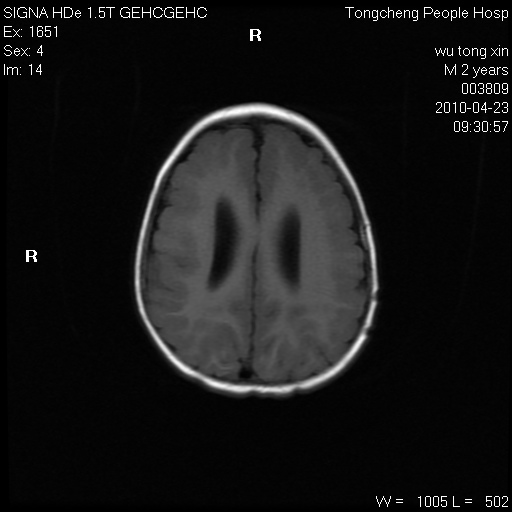

以下是引用赵物学在2010-4-25 12:43:00的发言:[br]巨脑回[br]侧脑室后角低密度影考虑hie或肾上腺脑白质营养不良?[br][br][本贴已被 赵物学 于 2010-4-25 12:51:28 修改过]

以下是引用gaoxiao在2010-4-25 16:54:00的发言:[br]巨脑回畸形。脑白质髓鞘化不良

以下是引用pujunzhi在2010-4-25 21:35:00的发言:[br]考虑 1双侧大脑皮质发育不良 2轻度脑积水 3双侧脑室后角旁片状长t1长t2信号,需继续观察,因为正常小儿此处脑白质的髓鞘化时间可以延迟到4-6岁,才显示正常。